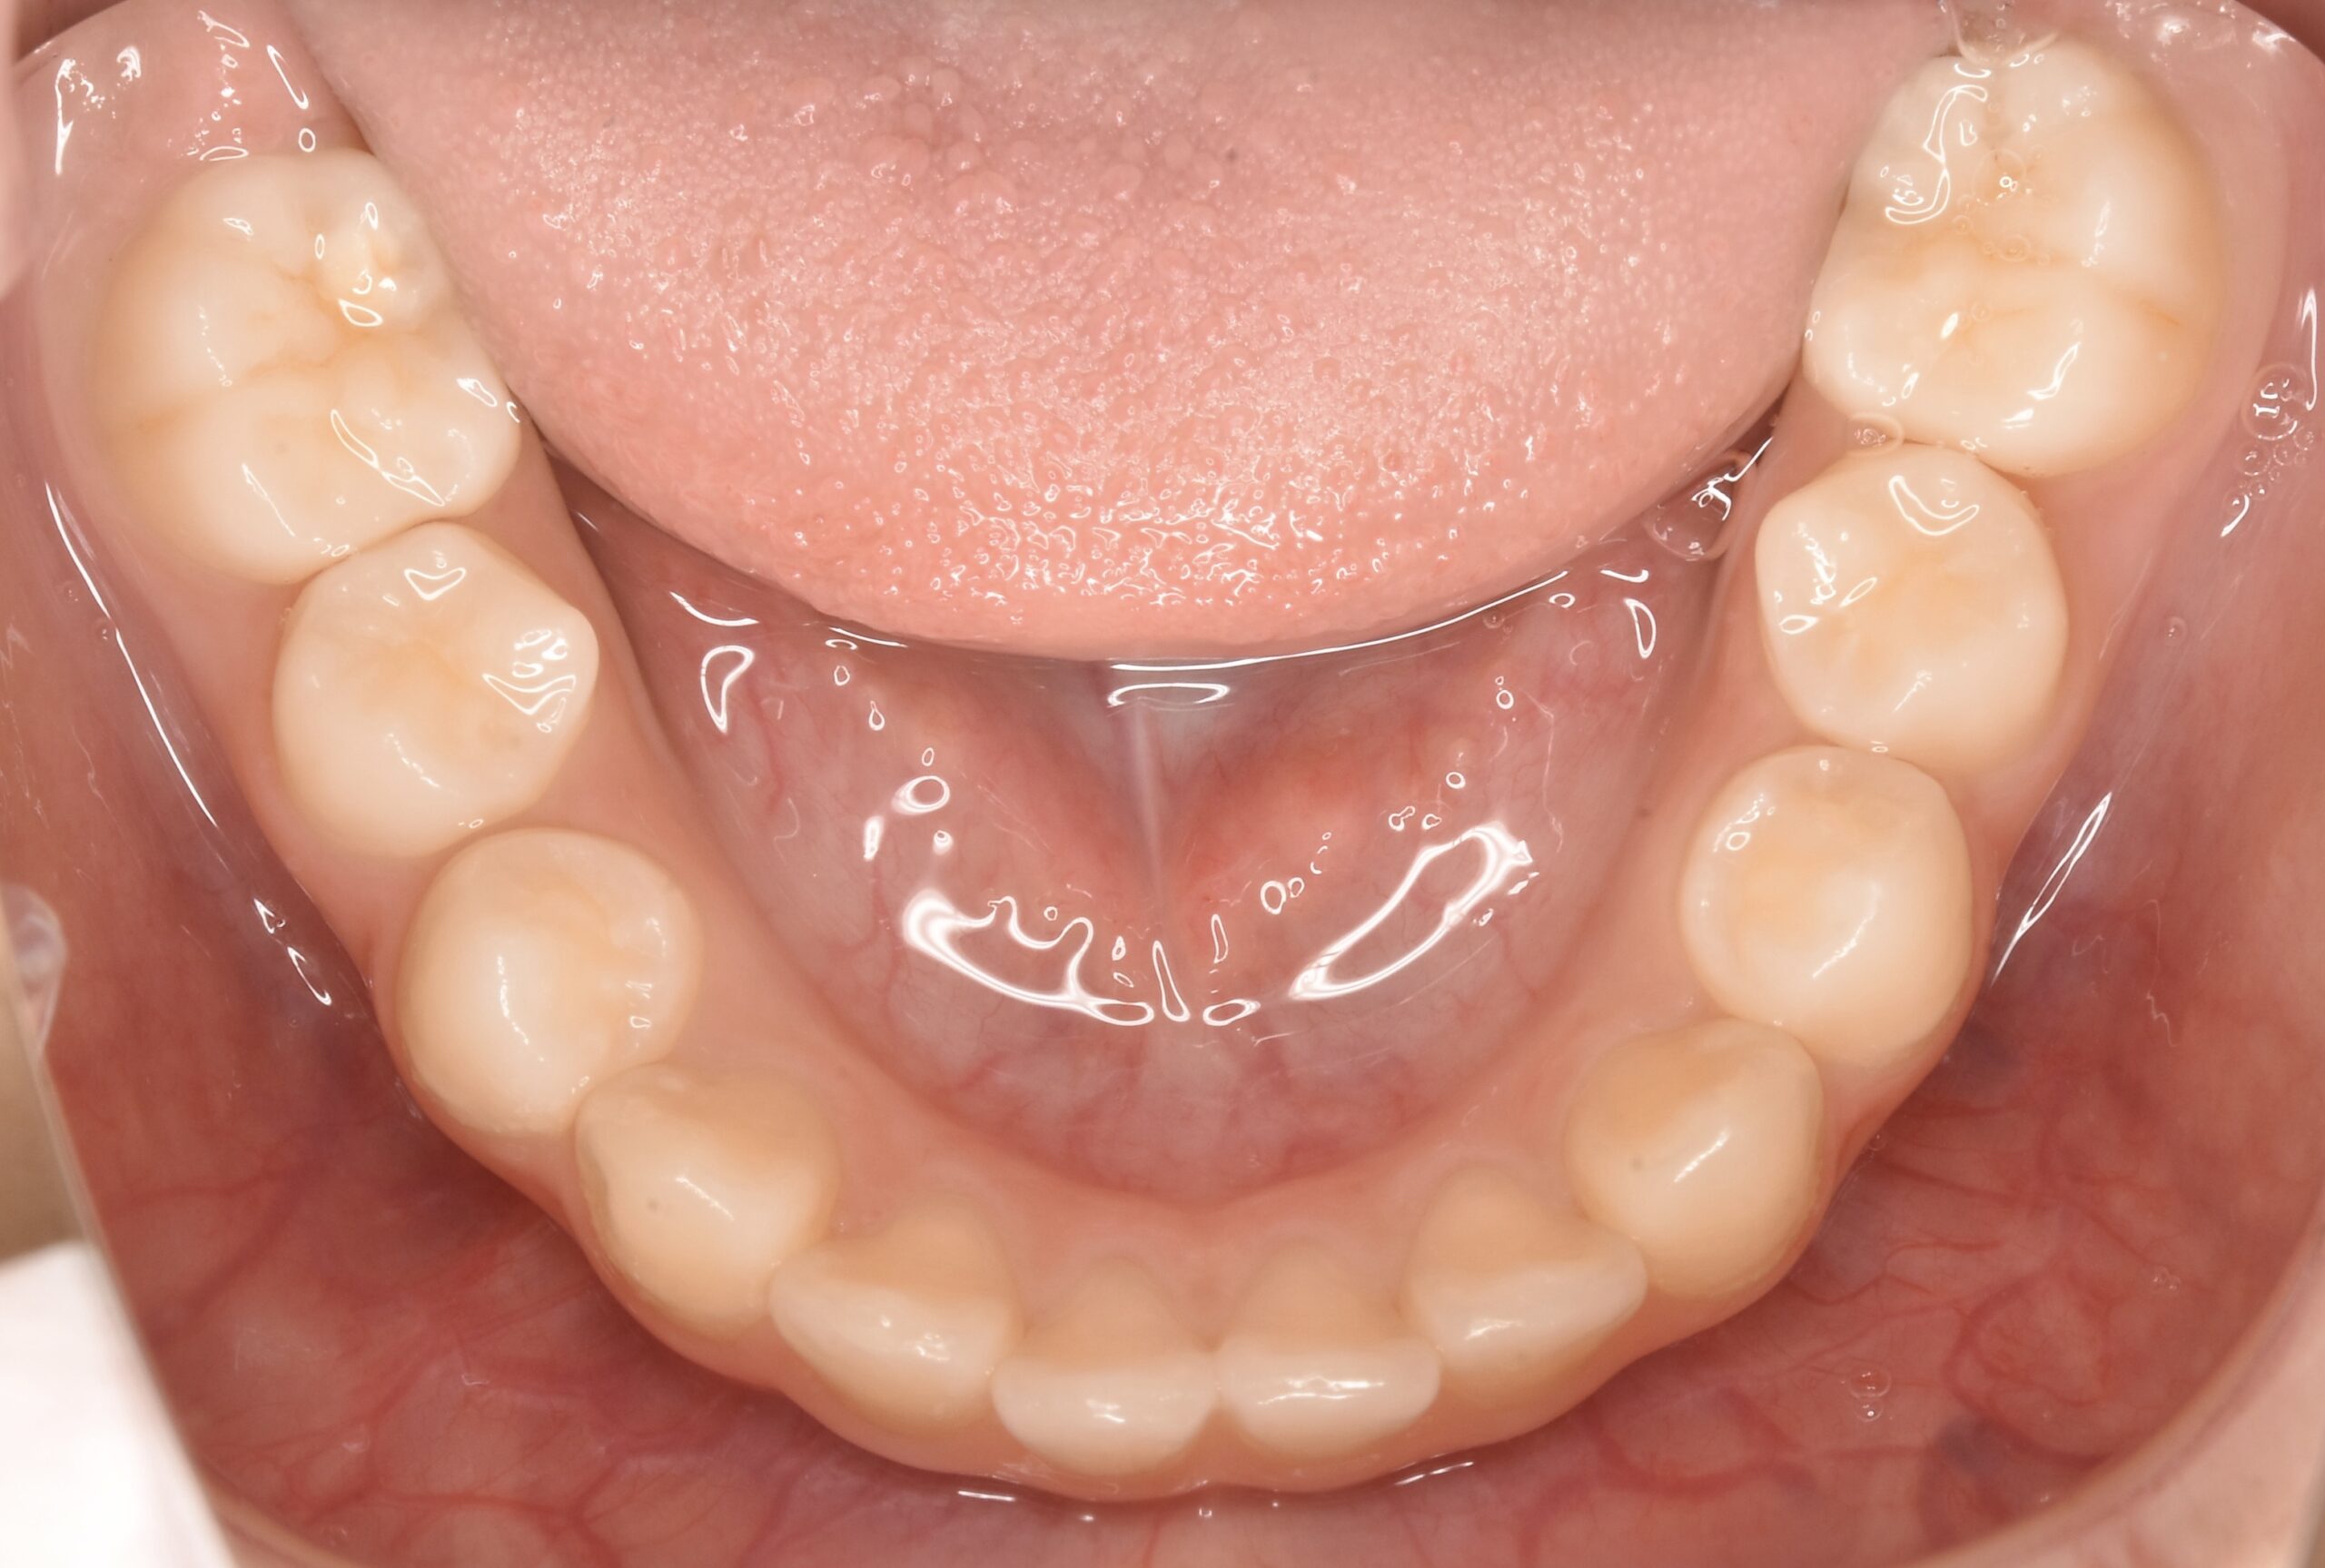

- AFTER

| 治療内容 | 永久歯がきれいに並ぶスペースが不足していたため、上あごの成長を促す顎顔面矯正装置(拡大装置)を使用しました。 現在、第2大臼歯の萌出経過を観察中です。 永久歯の生え変わりに合わせて歯並びや噛み合わせを確認しながら、必要に応じて継続的な管理を行っています。 false |

| 使用装置 | 顎顔面矯正装置(拡大装置) false |

| 治療期間 | 約2年(経過観察期間を含む) false |